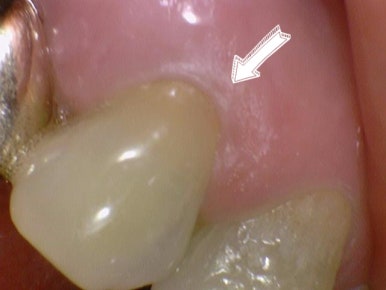

치경부마모 치료법 레진 전후 사진

치경부마모증의 치료법은 여러가지가 있는데 가장 흔한 치료법은 레진치료입니다. 그 패인 부위를 레진으로 떼우는 것입니다.

치경부 마모 가 있어서 시린 환자분의 치아를 레진으로 떼운 사진을 볼게요. 저희 치과에서 직접 치료하고 찍은 사진이랍니다.

치경부 마모 레진 치료 전 후

시린 치아 마모 레진 전후

치경부가 패여서 물과 양치질에 의해 시리거나, 찬바람을 쓰읍하고 들이마시기만 해도 시릴 수 있어요. 이런 경우 위와 같이 레진으로 때우면 그 증상은 대부분 사라지게 됩니다.